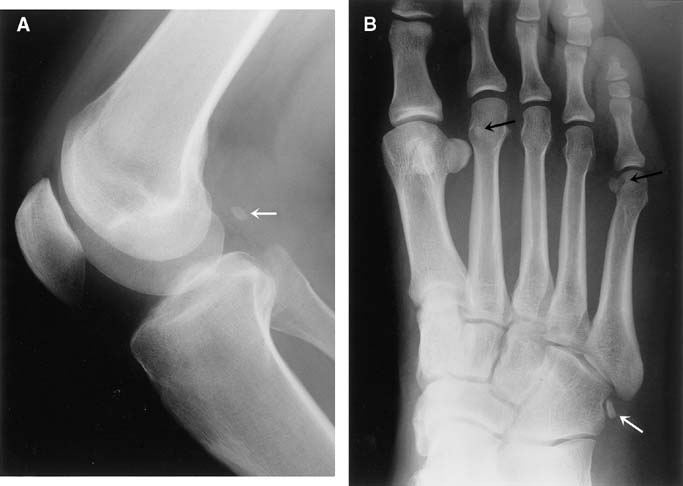

Анатомия: Блоки и сесамовидные кости в деталях